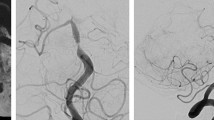

Example of vasa vasorum around a giant, partially-calcified vertebral artery aneurysm in a 25-year-old patient. Twelve years prior to admission, a giant fusiform aneurysm of the right vertebral artery was found and surgically treated by proximal exclusion (“clipping”) of the parent vessel. On admission, the patient’s CT demonstrated a partially-calcified aneurysm (asterisk) with peripheral haemorrhage (arrowhead). Angiography (right vertebral artery, lateral projection) indicates that the aneurysm is completely excluded. However, there are many small vessels seen surrounding the aneurysm (arrows) that represent the vasa vasorum. This case illustrates that despite exclusion of the parent artery and the aneurismal lumen, the vessel-wall disease is still active

The primary cause for the dissection is unknown. However, one might presume that atherosclerosis can—via a chronic inflammatory response—lead to a thinning of the media and cause vascular rupture within the adventitia. The haemorrhage stops the further dissection of the media; otherwise, an acute transmural dissection with subarachnoid haemorrhage occurs [15, 25, 26]. The increase in number and size of the vasa vasorum fits well with this concept. Since the biological phenomenon is persisting, the effects may be still active, which explains why some cases of dissection continue to evolve even after therapeutic occlusion of the vessel (Fig. 3).